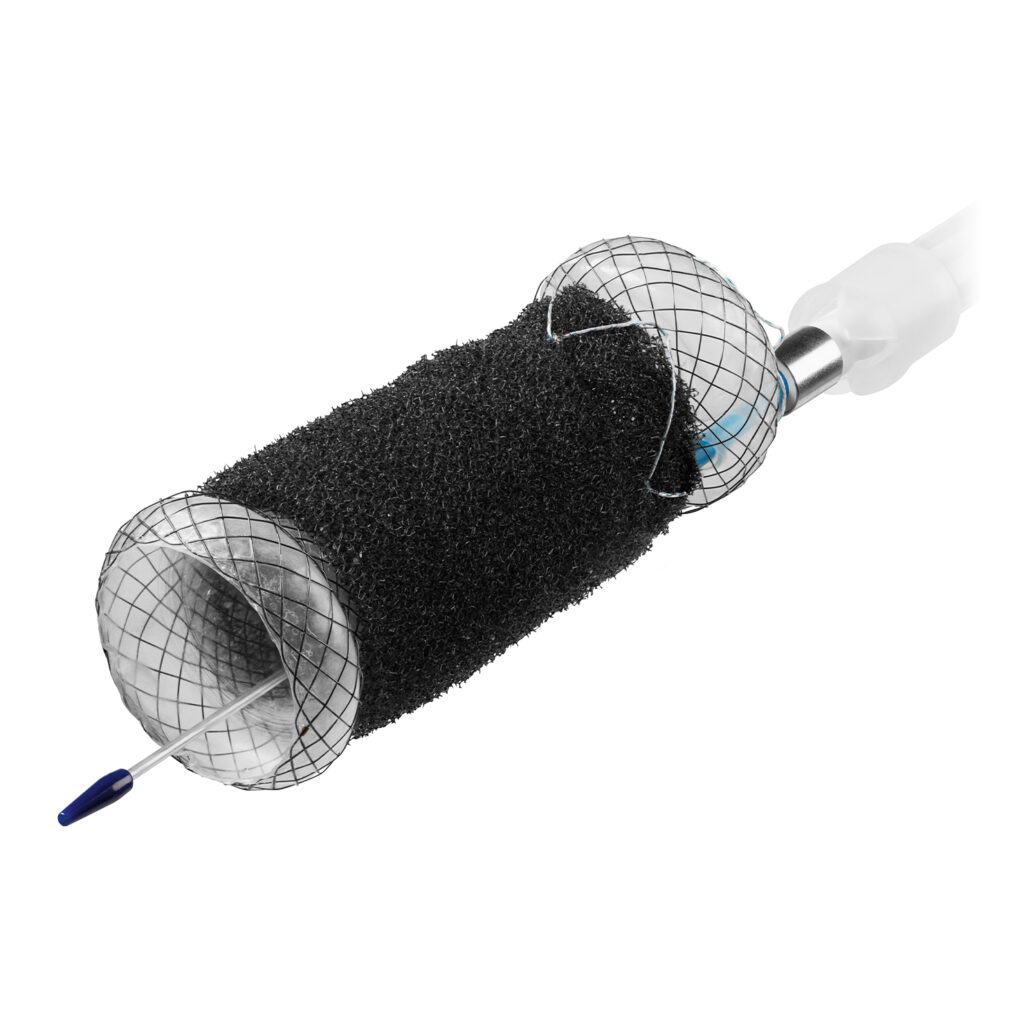

VAC Stent

The VacStent GI™ combines two reliable methods for the treatment of leakage and anastomotic insufficiency: while the fully encased stent completely covers the defects, the wound cavity is drained by continuous suction.

- Easy and precise placement of the stent by means of OTW (over-the-wire)